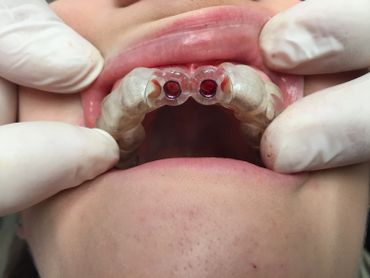

The Neodent® EasyGuide Sleeve is selected according to mesiodistal space and implant diameter.

Neodent® EasyGuide offers two sleeve diameters for optimizing positioning

The Neodent GM Guided Surgery Kit is a compact, easy to use guided surgery system. Clinicians can provide CT scan, digital photos, and impressions to a laboratory for precise implant guide fabrication. Temporary teeth can be made and the lab will know the depth, angle, and timing of the connection of the implant. This allows you better esthetics and provides the patient teeth the same day with less chair time.